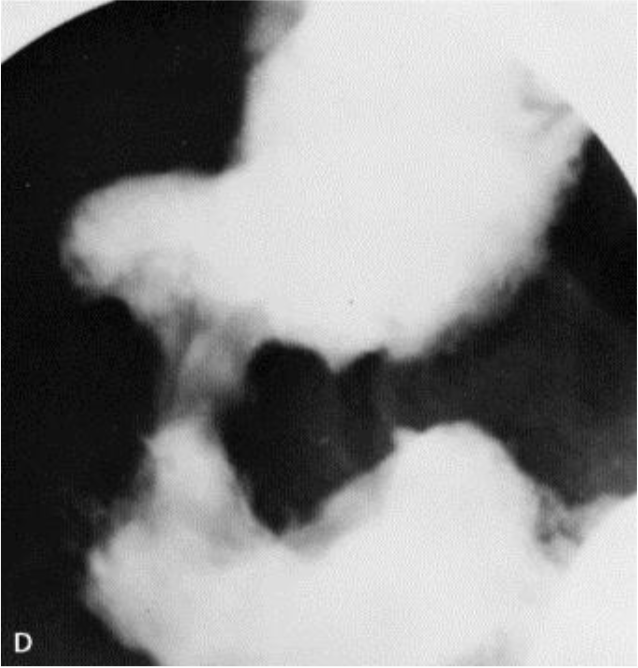

A 60-year-old patient presented with changes in bowel movements and bleeding per rectum. Barium enema showed apple core appearance of the colon. What is the diagnosis?

A. Colon cancer